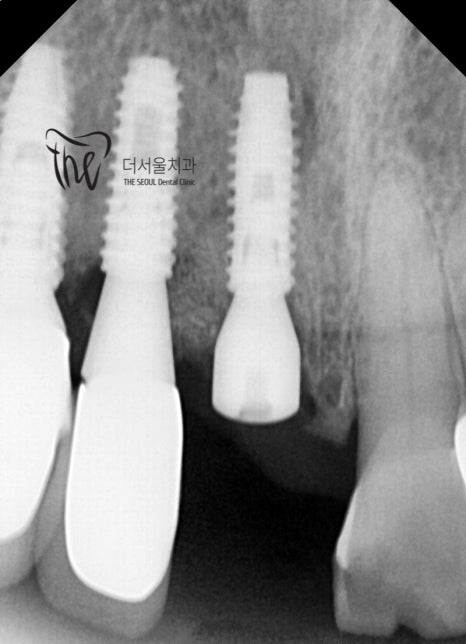

『앞니, 어금니 임플란트 동시 진행』

앞니 임플란트 는 남아있는 양 옆에 있는

보철 및 치아와의 거리를 잘 측정해서 가운데에

잘 심어드렸습니다. 가뜩이나 뼈가 얇은데

또 공간도 협소했던지라 여간 쉽지는 않았습니다.

어금니 쪽은, 상악동거상술 및 뼈이식술을

같이 병행하면서 시술을 진행했습니다.

잘 심겨진 것을 볼 수 있죠?